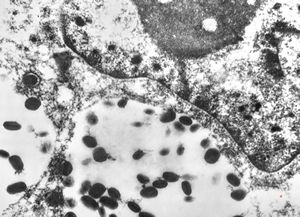

F, 24y. | molluscum contagiosum … virions

F, 24y. | molluscum contagiosum

F, 24y. | molluscum contagiosum